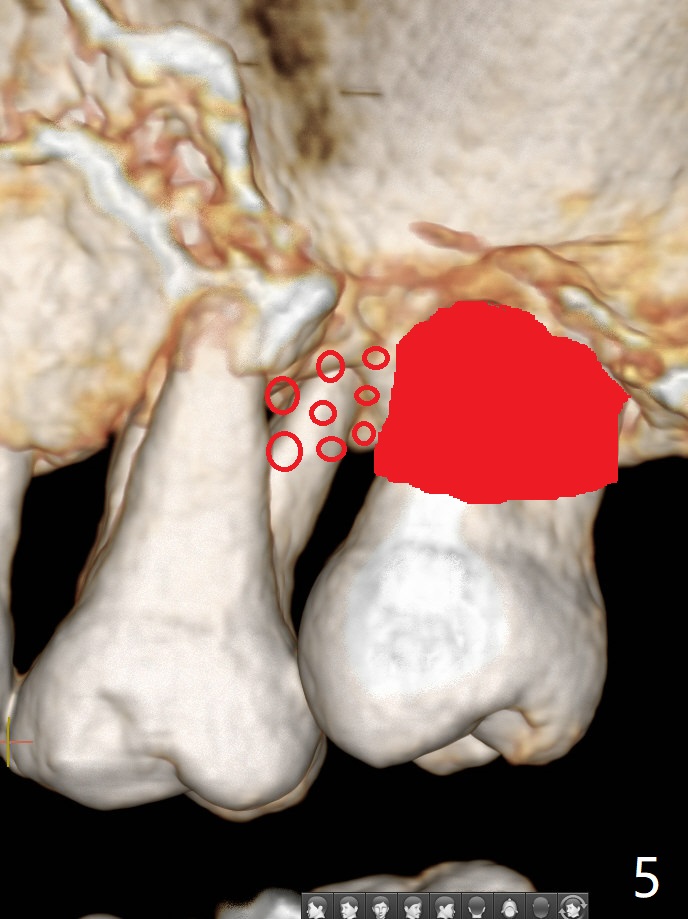

45岁女右上7严重骨质吸收终于开始出现症状(图一),虽然邻牙(6)骨质吸收也明显(图二,四,六,八,十),但是保留它,远中颊侧(DB),腭侧(P)根成为骨粉(图三,五,七,九,十一:红圆圈)支架。